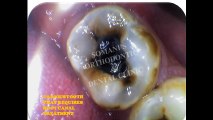

Root canal treatment (endodontics) is a dental procedure used to treat infection at the centre of a tooth. Root canal treatment is not painful and can save a tooth that might otherwise have to be removed completely